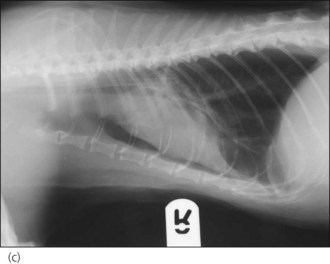

In the author’s experience, neoplasia and congestive heart failure (see Ch. 31) are the two most common causes identified in cats (see Figures 32.1-32.4).

image image image image

Figure 32.4 Right lateral and dorsoventral thoracic radiographs of a cat with idiopathic chylothorax (a, b) before and (c, d) after thoracocentesis. The post-drainage films were taken the day after under general anaesthesia; an oesophageal stethoscope is visible.